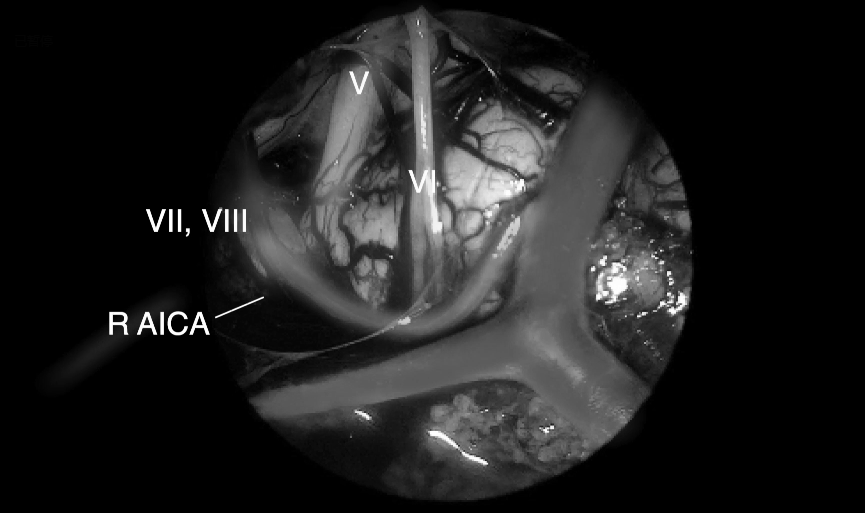

肿瘤取出后,可见清晰的周围血管神经。R VI,右侧展神经;LVI,左侧展神经;R AICA,右侧小脑下前动脉;L AICA,左小脑下前动脉;R VA,右侧椎动脉;LVA,左侧椎动脉;Basilar ,基底

VI,展神经;VII,面神经;VIII,前庭蜗神经;R AICA,右侧小脑下前动脉;